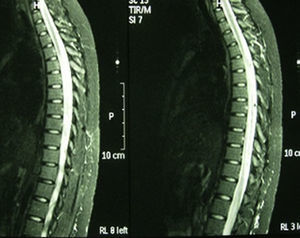

Casos clínicosCaso 1. Mujer de 34 años, caucásica, con antecedentes de neuritis óptica en el ojo derecho hace 8 años. Ingresó por cuadro de malestar abdominal, vómito y fiebre, seguido a las 48 h de parestesias y debilidad ascendente en miembros inferiores, retención de orina y heces, y disminución de la agudeza visual en el ojo izquierdo. En el interrogatorio de conectivopatías refirió xerostomía, xeroftalmia, sequedad vaginal y cutánea. La exploración neurológica presentó paraparesia, con balance muscular de 1/5 en el miembro inferior izquierdo, 0/5 en el miembro inferior derecho y 2/5 en el miembro superior derecho, hiperreflexia difusa, reflejo cutaneoplantar extensor, nivel de hipoestesia para sensibilidad térmica y dolorosa en dermatoma D4-D5 de predominio derecho y déficit de sensibilidad profunda en el miembro inferior izquierdo. Prueba de Schirmer bilateral inferior a 5mm. En la analítica destacaba velocidad de sedimentación globular 48mm/h, proteína C reactiva 2,74mg/dl, anticuerpos antinucleares (ANA) + patrón moteado 1/320, anti-Ro/SSA y anticuerpos antiacuaporina 4 positivos y anticuerpos antifosfolípidos negativos. Vitamina B12, ácido fólico, serología (lúes, Brucela, Borrelia, VIH, VHC, VHB), proteínas de Bence Jones, crioglobulina, cobre en suero, niveles de enzima convertidora de angiotensina, homocisteína y coagulación, normales. Resonancia magnética (RM) de columna cervical y dorsal: lesión intramedular desde C5 hasta D2. RM cráneo (fig. 1): presencia de múltiples lesiones en la sustancia blanca en secuencias T2 y FLAIR. Potenciales evocados: respuesta P100 alargadas bilateralmente, siendo mayor en el lado derecho. Con diagnóstico de SS, se inició tratamiento con bolos de metilprednisolona por vía intravenosa seguido de prednisona por vía oral a 50mg/día y azatioprina, consiguiéndose un aumento progresivo de la agudeza visual, si bien persiste un escotoma periférico temporal superior en el ojo derecho. Recuperación del balance muscular y del control de esfínteres, con deambulación sin apoyo a los 15 meses, sin un nuevo episodio en los últimos 2 años.

Resonancia magnética de cráneo en secuencias T2 y FLAIR, con presencia de múltiples lesiones en la sustancia blanca a nivel corticosubcortical, periventricular, periauriculares y en corona radiada derecha. Lesión de mayor tamaño desde el brazo posterior de la cápsula interna derecha hasta el pedúnculo mesencefálico derecho.

Caso 2. Mujer de 63 años de edad, caucásica, con antecedentes personales de hipotiroidismo autoinmune, hipercolesterolemia y 3 episodios previos de mielitis cervical de origen inflamatorio, con buena respuesta a bolos de metilprednisolona. De nuevo ingresó por cervicalgia acompañada de disminución de fuerza en los miembros superior e inferior izquierdos, pérdida de sensibilidad y disestesias en el antebrazo y la mano izquierda, con disminución de la agudeza visual progresiva e incontinencia urinaria. En la anamnesis refirió xeroftalmia y xerostomía de 3 años de evolución. La exploración presentó un balance muscular en el miembro superior izquierdo de 2/5 distal y 3/5 proximal, en el miembro inferior izquierdo 2/5 proximal y distal, y en el miembro inferior derecho 4+/5 proximal. Reflejo cutaneoplantar extensor bilateral. Fondo de ojo normal. Prueba de Schirmer positiva. Analítica: hemograma, bioquímica, hormonas tiroideas, proteinograma, vitamina B12 y ácido fólico, normales. ANA, anticuerpos anticitoplasma de neutrófilo y anticuerpos antifosfolípidos, negativos. Anticuerpos antiacuaporina 4 positivo. Serología para VIH, virus de la hepatitis A, VHB, VHC, Borrelia y Brucella, negativos. Punción lumbar con valores en líquido cefalorraquídeo de 8 leucocitos/mm3, glucosa 50,3mg/dl, proteínas 65,2mg/dl, adenosina deaminasa 4,8 U. Cultivo para hongos, micobacterias, criptococo y tinción de Gram, negativos. RM de columna cervical: afectación de médula cervical desde proceso odontoides a C5. Potenciales evocados: se obtienen respuestas reproducibles en ambos ojos, aunque latencia aumentada en el ojo izquierdo y límite en el derecho, compatible con neuritis óptica. Biopsia de glándulas salivales: lóbulos de la glándula salival con 2 agregados compactos de más de 50 linfocitos maduros, compatible con SS. Se inició en esta ocasión tratamiento con ciclofosfamida quincenal durante 3 meses y azatioprina, con importante recuperación funcional progresiva hasta alcanzar un balance muscular 5/5 al primer año del tratamiento y sin nuevo episodio de mielitis en los últimos 3 años. La RM de cráneo y columna completa actual no muestra áreas de mielitis activa.

Respecto al diagnóstico, la RM es su prueba determinante. Los estudios muestran anormalidad de la señal con hiperintensidad en T2, realce con gadolinio y edema del cordón medular. No existen imágenes específicas según la etiología, si bien múltiples pequeñas lesiones parecen indicativas de LES, mientras que lesiones muy extensas y anormalidades en varios niveles son más indicativas de vasculitis12. En la RM cerebral podemos encontrar lesiones desmielinizantes en T2/FLAIR, con marcada afectación, como en nuestro caso 1. En el estudio del líquido cefalorraquídeo se puede observar inflamación del cordón medular, con pleocitosis o valores elevados de IgG. En el estudio inmunológico básico podemos encontrar los anticuerpos antimielina (que pueden predecir la evolución de un síndrome clínicamente aislado hacia la esclerosis múltiple) y los anticuerpos antiacuaporinas 4. La recurrencia de la MT se ha asociado a la existencia de anticuerpos anti-Ro/SSA13. Sin embargo, es precisamente nuestro caso de SS con episodios de repetición (caso 2) el que no presenta anticuerpos anti-Ro/SSA ni anti-La/SSB, basándonos para su diagnóstico en criterios clínicos e histológicos.